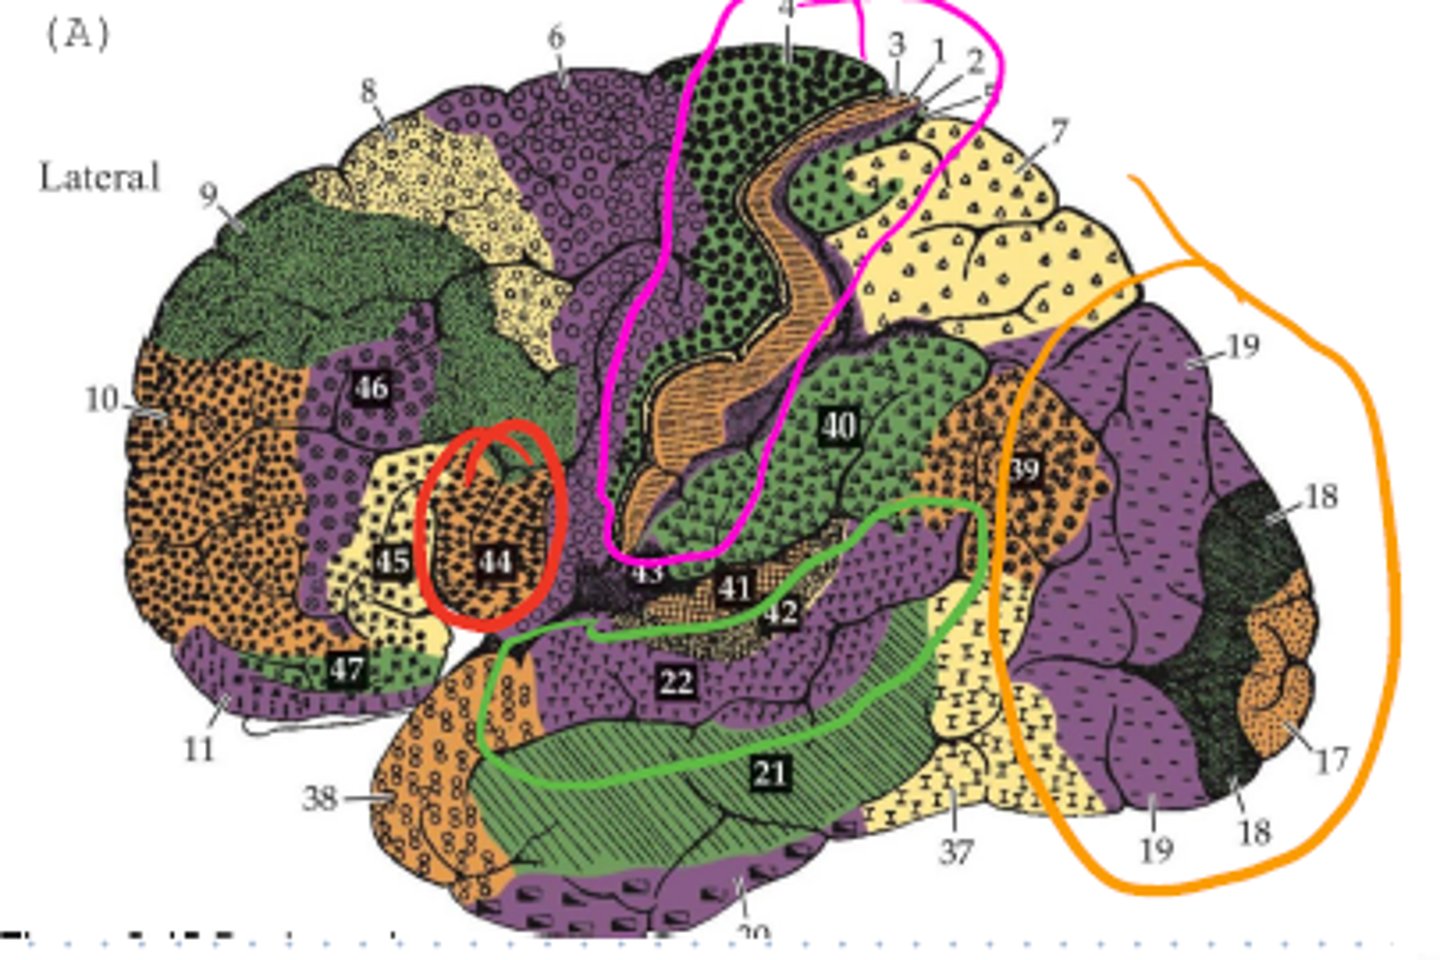

What # is the Primary Visual Cortex?

what is the blue circle surrounding?

What is the main name of the pink area?

Name one structure that comes from it?

What number is the post central gyrus?

What area is the orange structure pointing to?